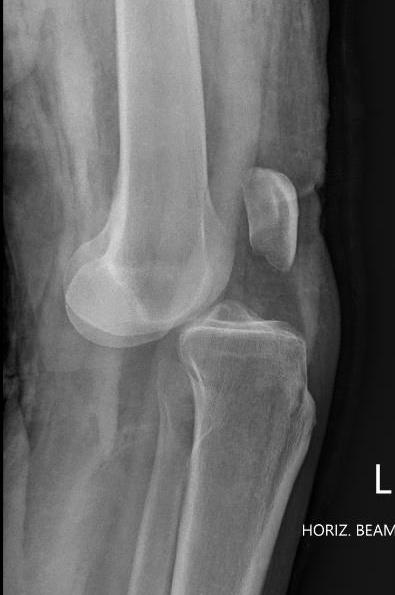

Posterior knee dislocations

Posterior dislocation of tibia

- second most common

- flexed knee, posterior force

- high risk of popliteal artery transection